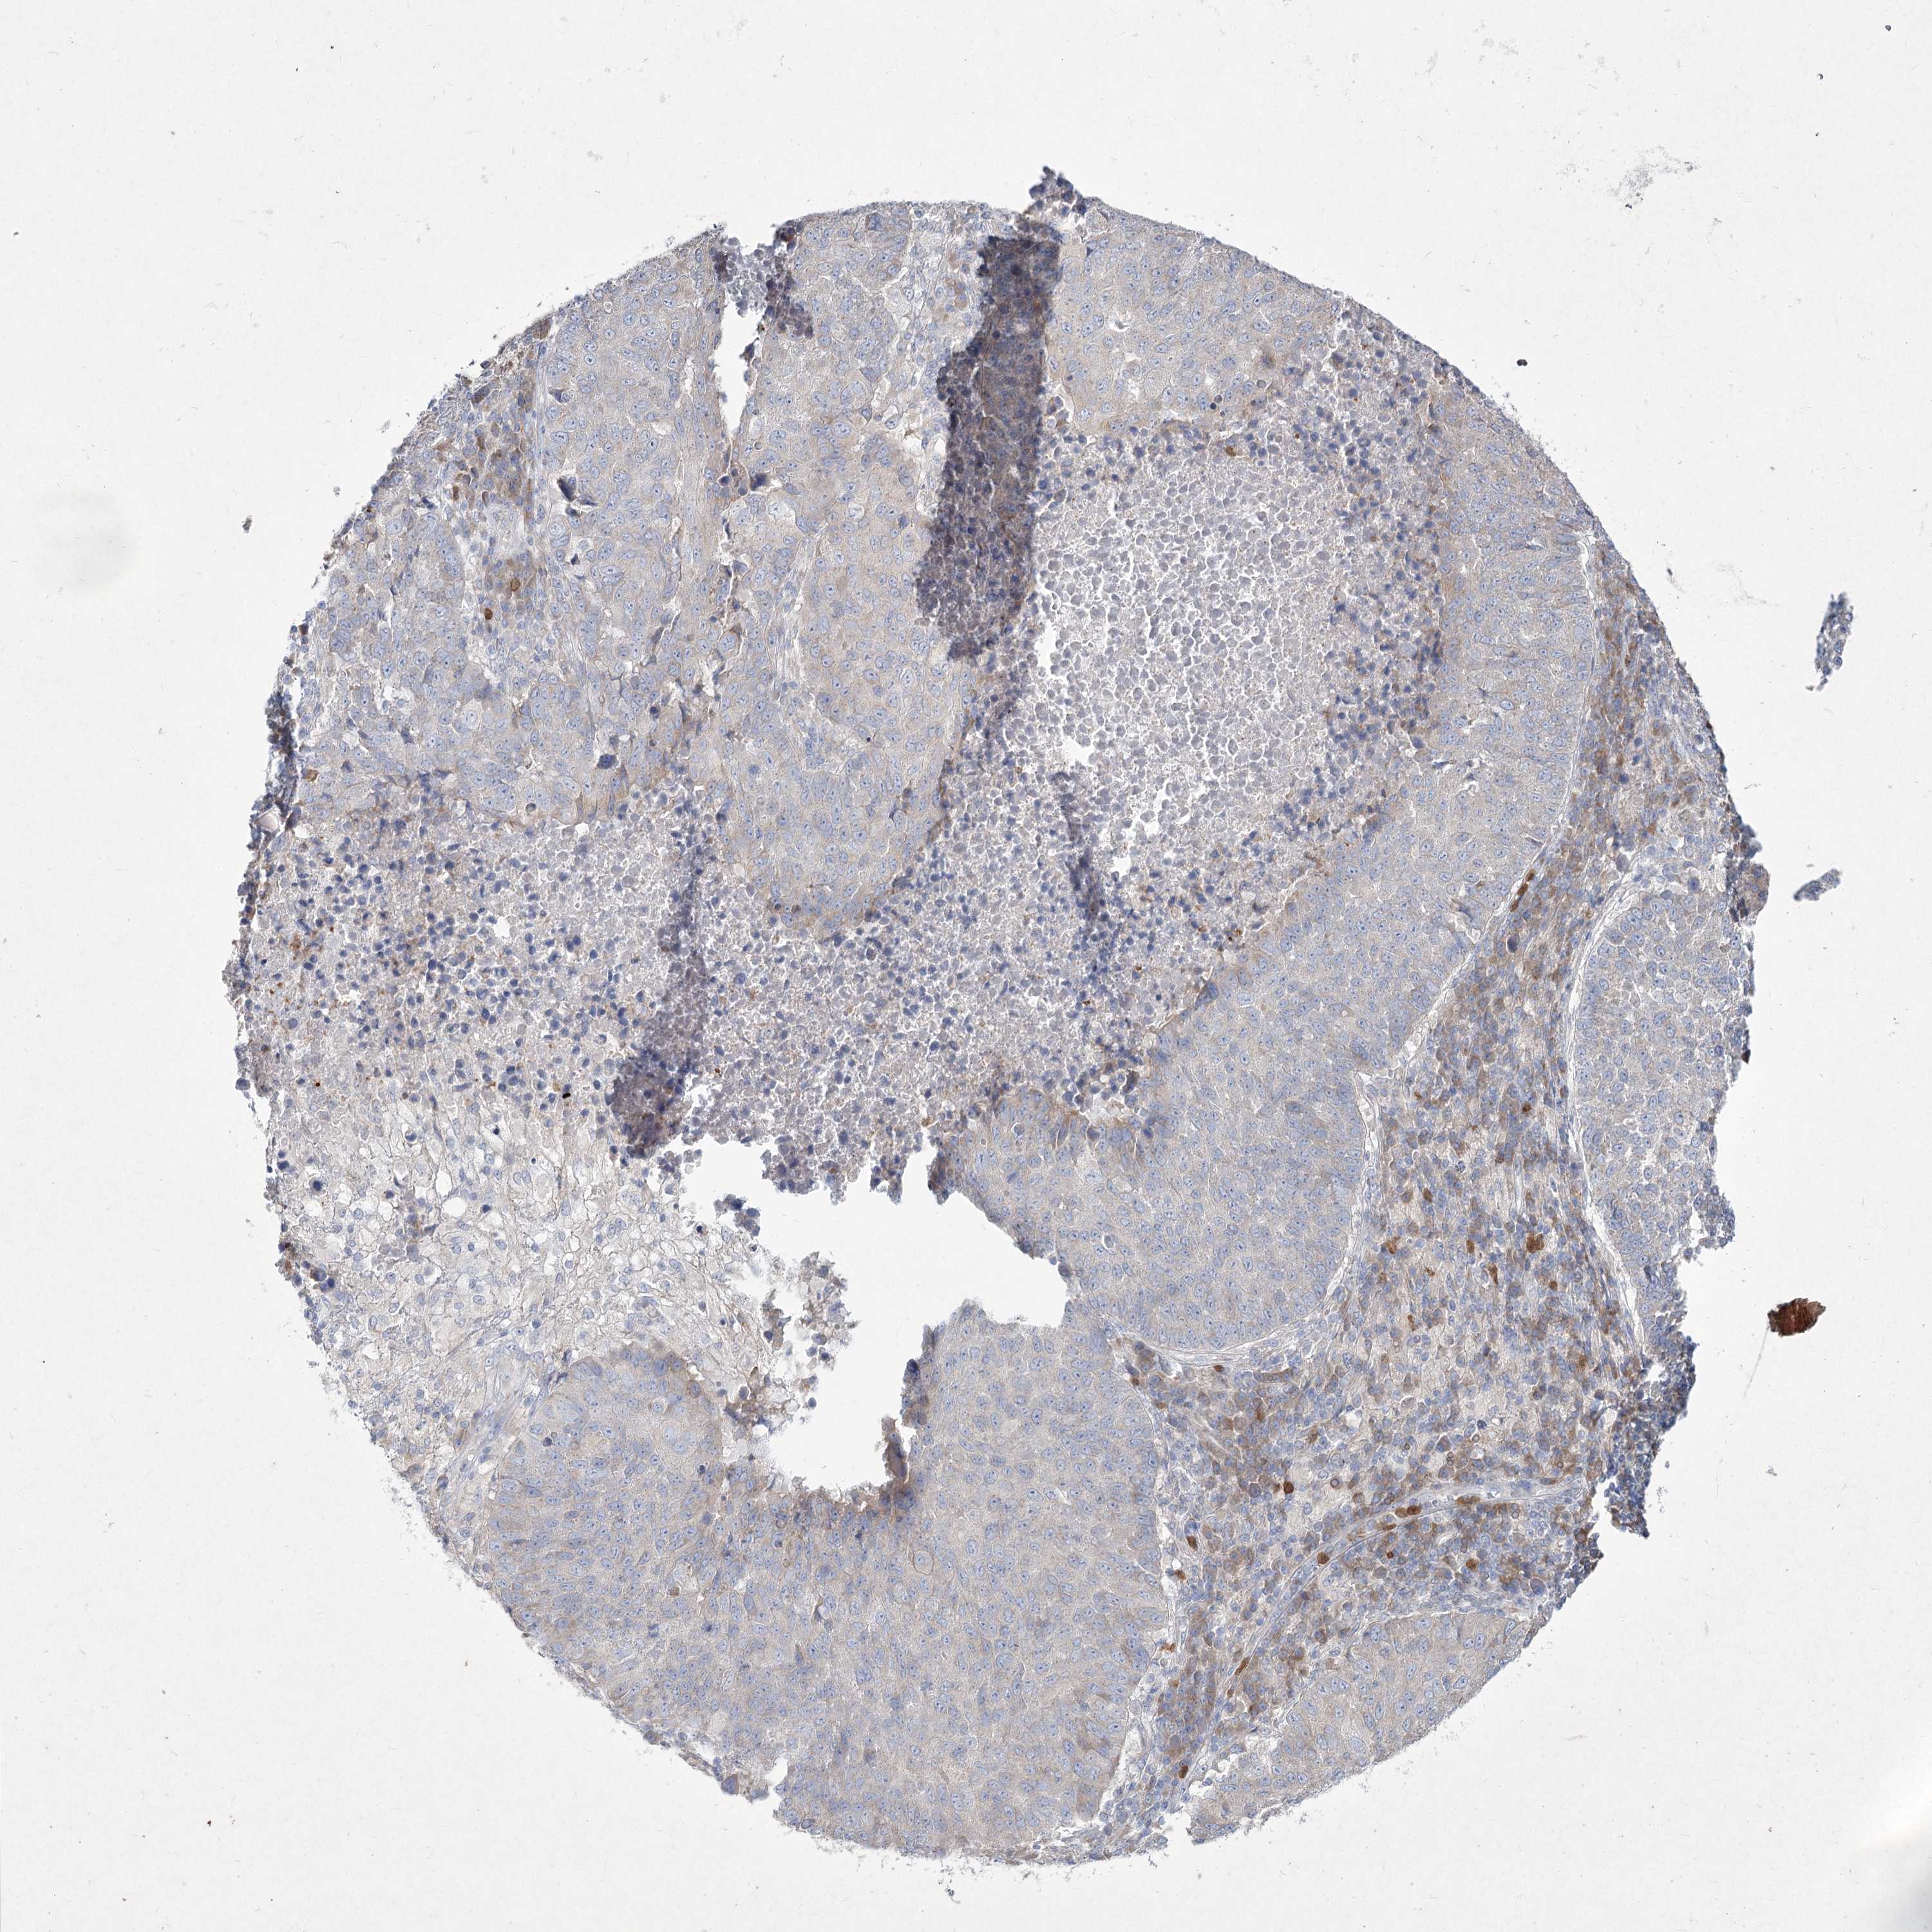

CANCER LUNG CANCER Show tissue menu

NIPAL4 is not prognostic in Lung Adenocarcinoma (TCGA)

Average pTPM 0.5

Number of samples 497